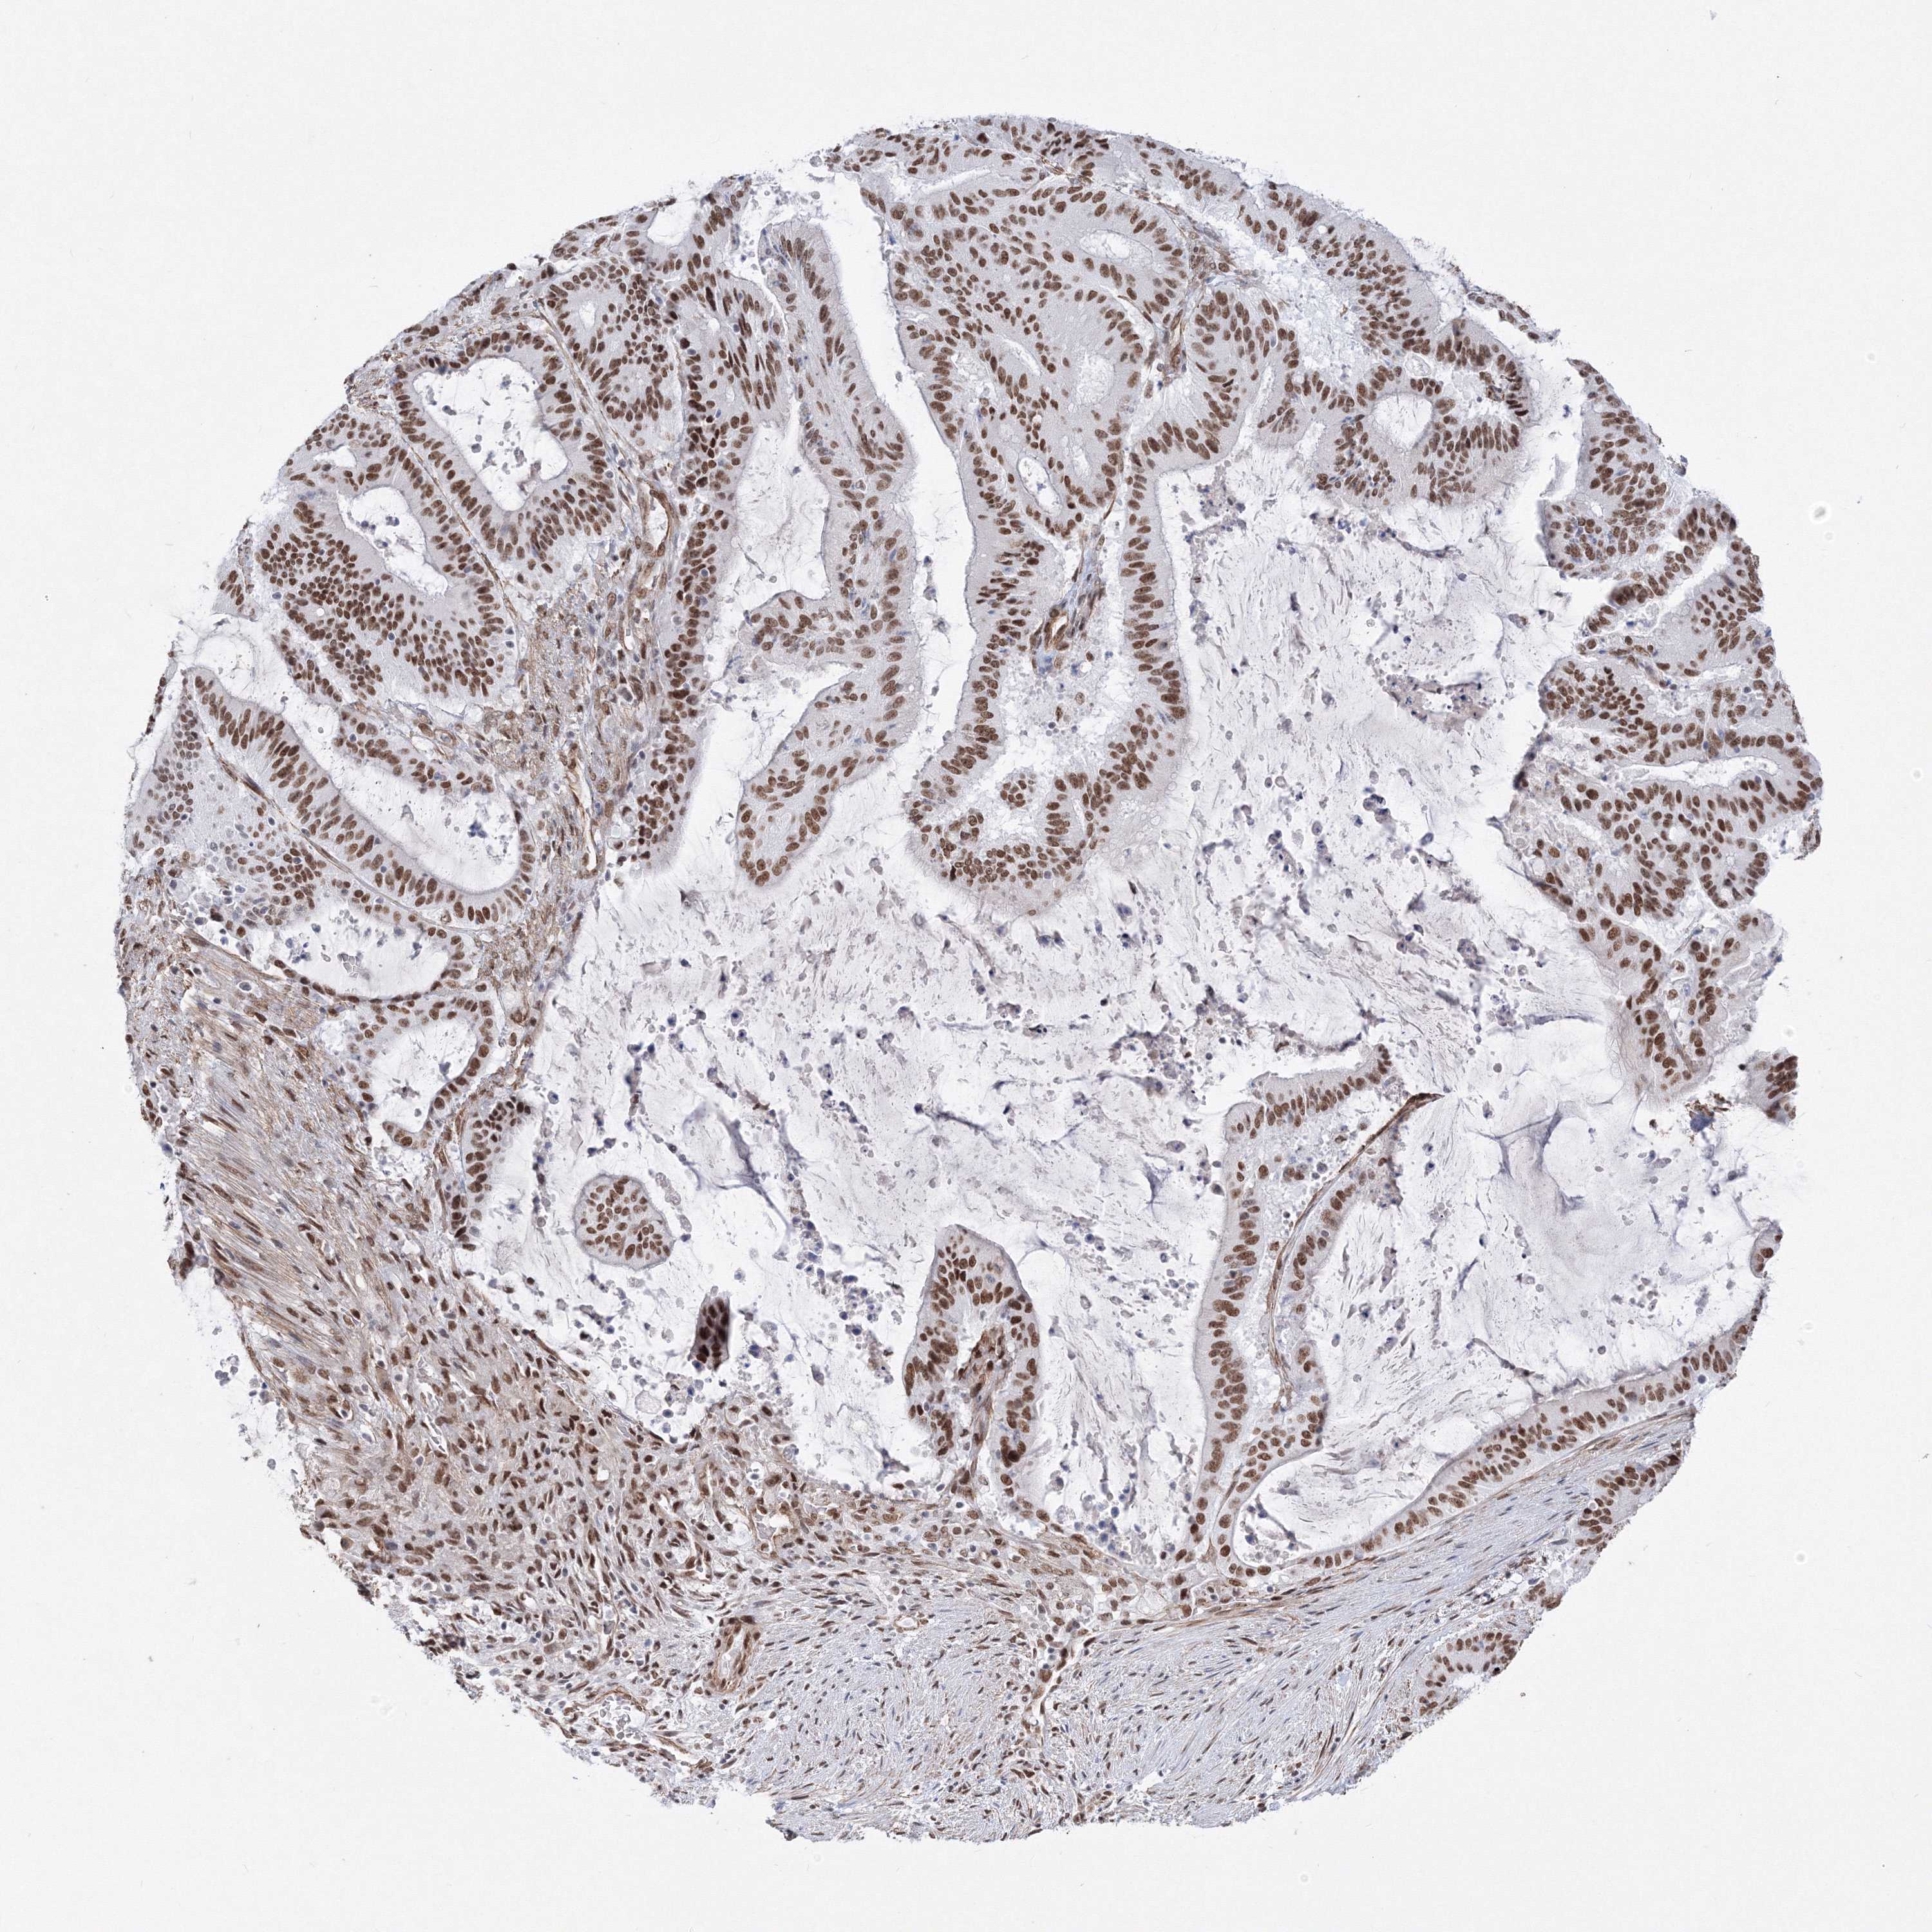

LIVER CANCER - Protein expressioni

A mouse-over function shows sample information and annotation data. Click on an image to view it in a full screen mode. Samples can be filtered based on level of antibody staining by selecting one or several of the following categories: high, medium, low and not detected. The assay and annotation is described here.

Note that samples used for immunohistochemistry by the Human Protein Atlas do not correspond to samples in the TCGA dataset.

Antibody stainingi

Antibody staining in the annotated cell types in the current human tissue is reported as not detected, low, medium, or high, based on conventional immunohistochemistry profiling in selected tissues. This score is based on the combination of the staining intensity and fraction of stained cells.

Each image is clickable and will lead to virtual microscopy that enables deeper exploration of all samples and also displays staining intensity scores, fraction scores and subcellular localization as well as patient and tissue information for each sample.

Antibody HPA036784

Staining

High

Medium

Low

Not detected

Intensity

Strong

Moderate

Weak

Negative

Quantity

>75%

75%-25%

<25%

None

Location

Nuclear

Cytoplasmic/membranous

Cytoplasmic/membranous,nuclear

Cholangiocarcinoma

Carcinoma, Hepatocellular, NOS